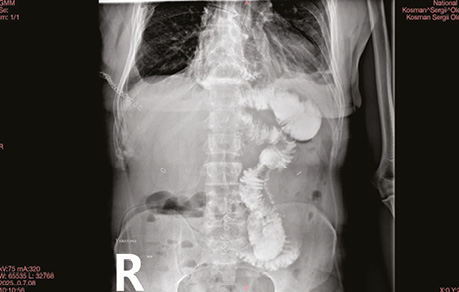

Плевральний дренаж забрано на 3-тю післяопераційну добу після рентгенографії грудної клітки.

Абдомінальний дренаж видалено на 6-ту післяопераційну добу після контролю пасажу (рис. 6).

Рис. 6. Післяопераційне контрастне дослідження пасажу кишкового вмісту